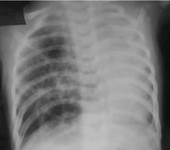

Avaliação da cianose neonatal

Malformação congênita da via aérea pulmonar (CPAM; antes conhecida como malformação adenomatoide cística congênita [MACC])

Do acervo de Ponthenkandath Sasidharan, MD; usado com permissão